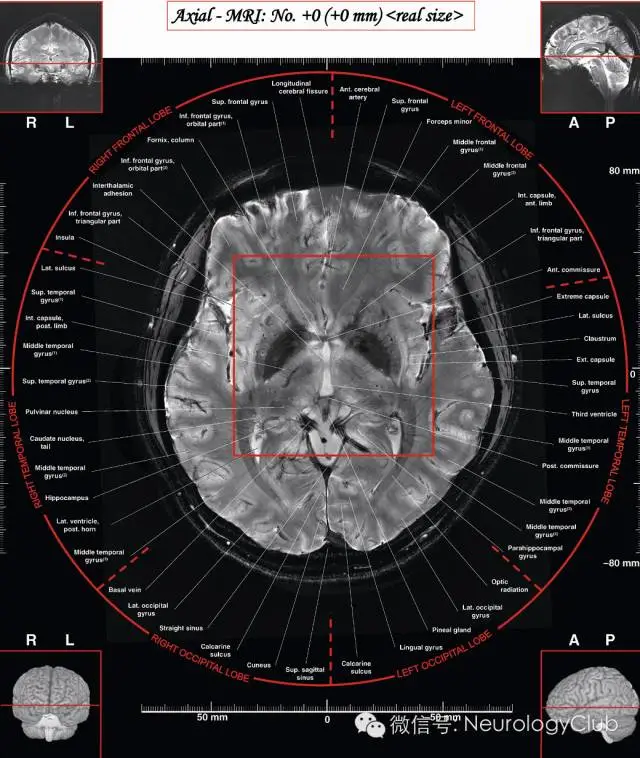

(图5:7T磁共振下的基底节区结构。引自:7.0 Tesla MRI Brain Atlas. Springer; 2nd ed. 2015)